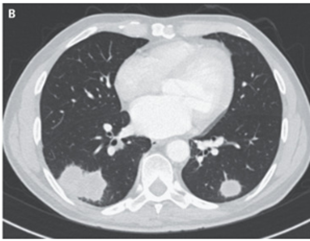

胸部CTでは肺結節が示唆された。